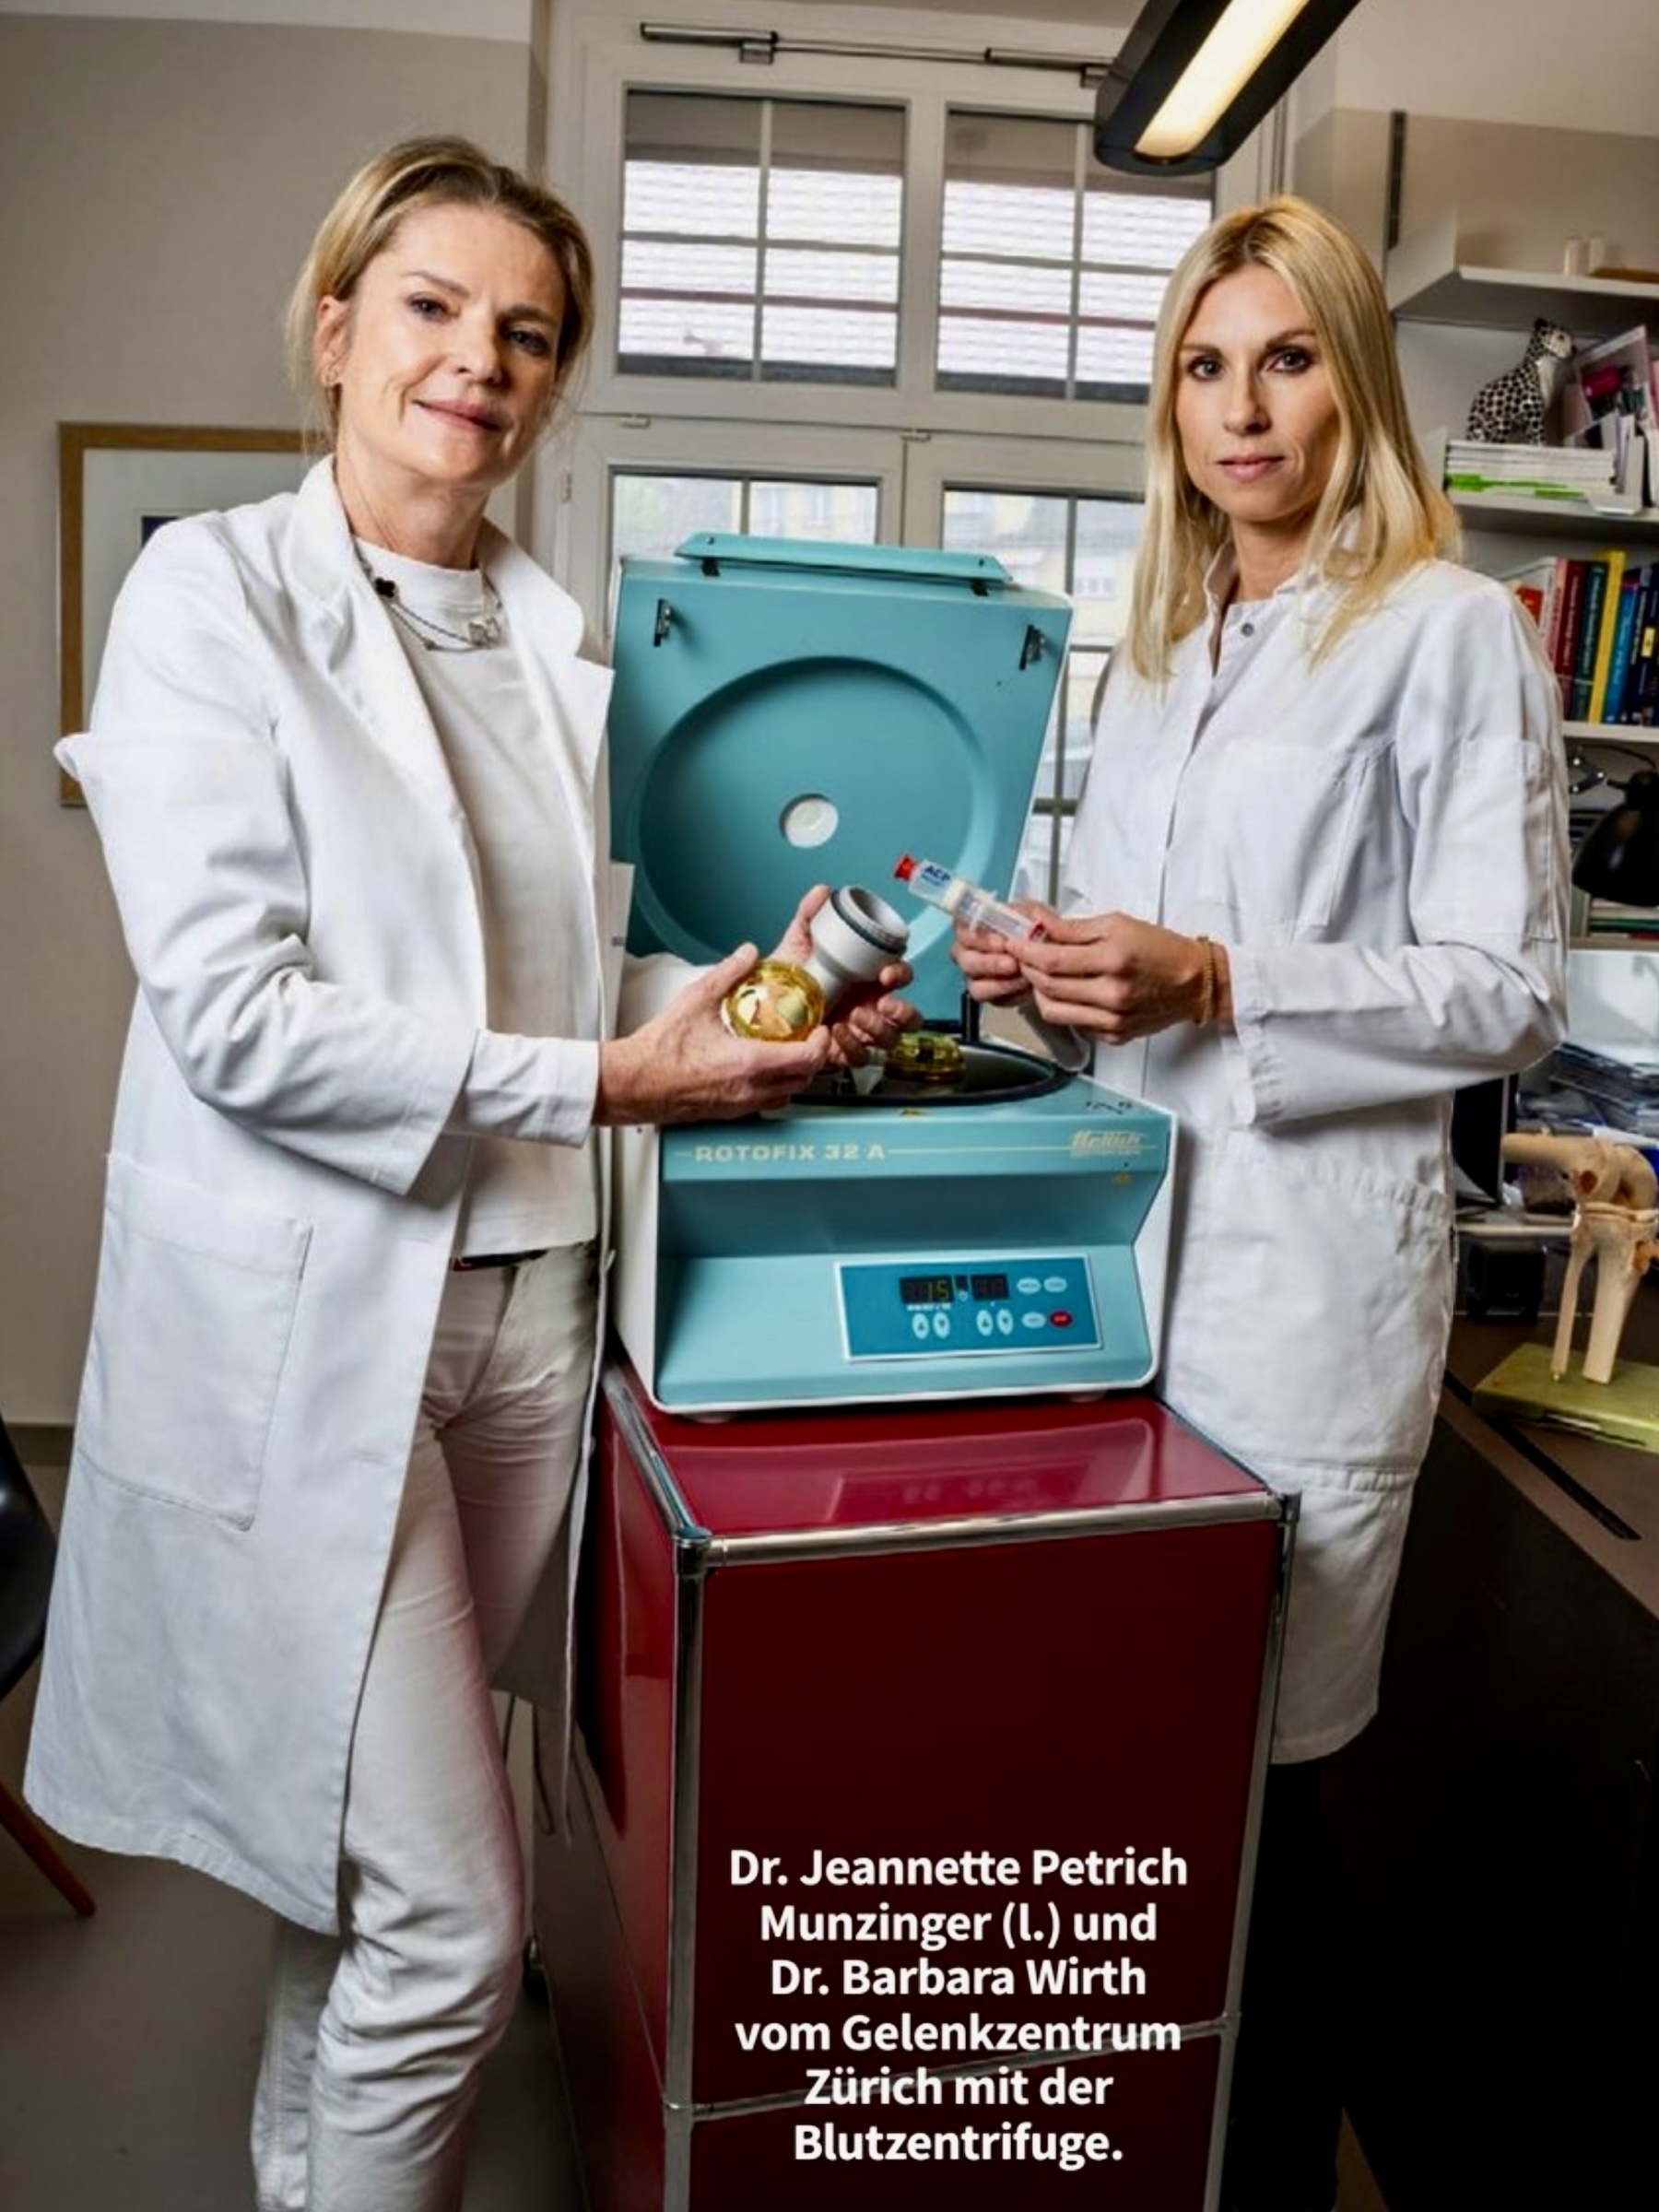

- Eigenbluttherapie